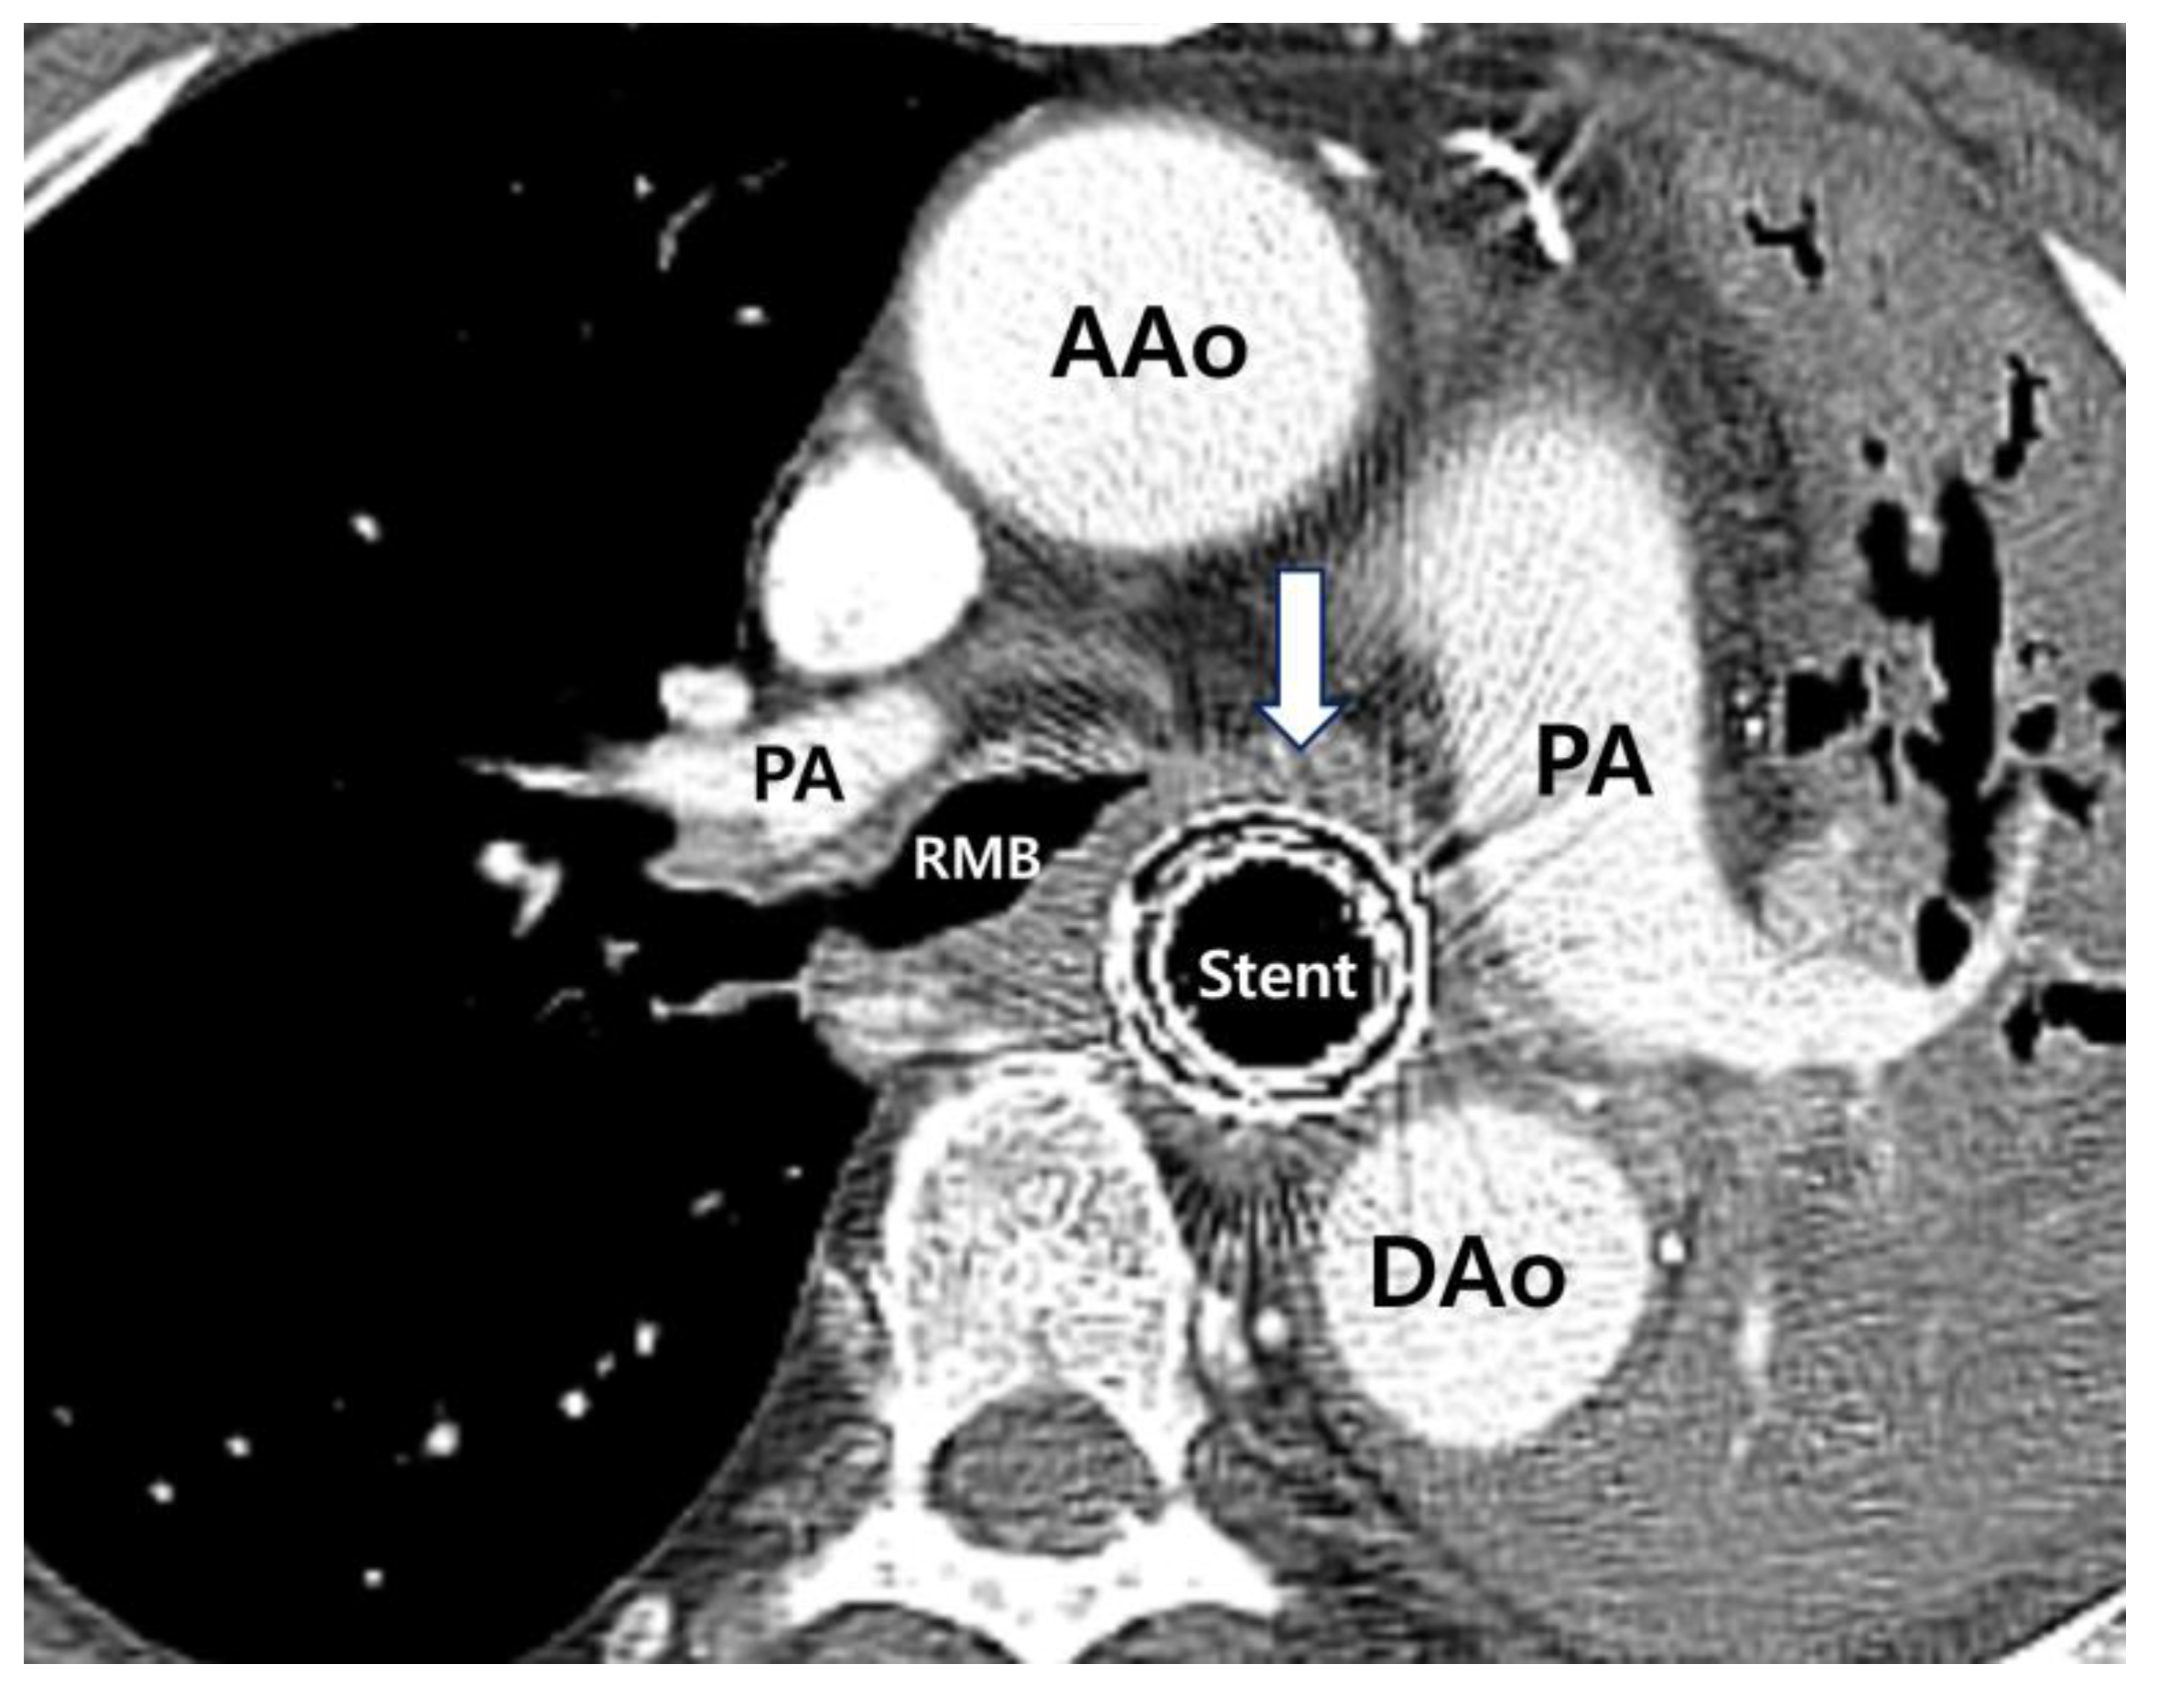

2. Case Report